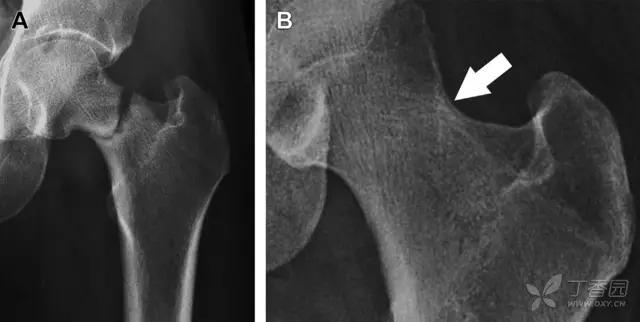

股骨颈应力性骨折在参加耐力运动的运动员中常见,且常发生在股骨颈压力侧。股骨颈基底部发现一垂直于骨皮质的线性硬化带可诊断这种类型的疲劳性骨折(图 8)。

图 8 长跑运动员股骨颈应力性骨折。X 片(A)和冠状位 CT 多维重建(B)图像示穿过股骨颈内侧皮质中的透亮区(箭头),周围硬化。骨折垂直于皮质

股骨颈张力侧的应力性骨折有可能发展为完全骨折(图 9)。

图 9 进食障碍患者股骨颈应力性骨折的张力侧。A 正位片示股骨颈完全骨折。B 2 周前的 X 片示局部骨量减少,正是后来发生骨折的位置(箭头)